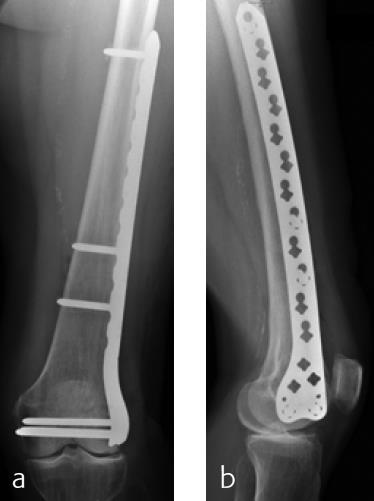

A 79-year-old woman fell downstairs at home and sustained a low-energy distal intraarticular femoral fracture. On conventional x-rays, the fracture seemed to be a unicondylar lateral split-type in rather osteoporotic bone (Fig 1). For detailed fracture analysis, a CT scan was performed that demonstrated a displaced lateral and nondisplaced medial condylar fracture (AO-33C1) (Fig 2). The fracture was very distal and therefore difficult to address with one lateral plate. Using VA technology in this situation provided the advantage of angulating the most distal anterior screw very close to the intercondylar notch in order to address the nondisplaced but fractured anteromedial condyle (Fig 3). Due to poor bone quality, a long plate was used to prevent a future periimplant fracture. Early follow-up showed uneventful healing with good function.